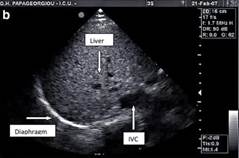

La ecografía también se ha utilizado para evaluar el grosor diafragmático (mm) en la zona de aposición del diafragma a la caja torácica. La zona de aposición es el área de la pared torácica donde el contenido abdominal llega a la caja torácica inferior (Fig.  2a). En esta zona, el diafragma se observa como una estructura formada por tres capas distintas (fig.  2b): una capa central no ecogénica bordeada por dos capas ecogénicas, el peritoneo y las pleuras diafragmáticas. Para obtener imágenes adecuadas de espesor diafragmático en modo M y modo 2D, es necesaria una sonda lineal de alta frecuencia (≥10 MHz). Un índice de engrosamiento diafragmático, la fracción de engrosamiento (FE) se puede calcular utilizando el modo M (FE = espesor al final de la inspiración - espesor al final de la espiración / espesor al final de la espiración) (22).

GRÁFICO 2.- ENGROSAMIENTO DIAFRAGMATICO. A Posición de la sonda para mediciones de espesor diafragmático en modo B y M en la zona de aposición con sonda de 10–12 MHz. B Ecografía en modo B del diafragma en la zona de aposición, a Pleura diafragmática ecogénica, b capa central no ecogénica, c capa peritoneal ecogénica.